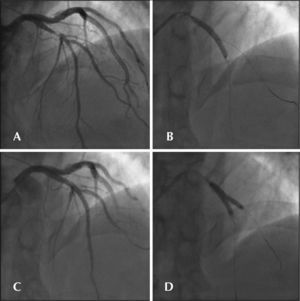

With the guide wire inside the stent, a new postdilation was performed with a noncompliant Quantum 4 × 12mm balloon at 12atm. The IVUS performed at that time revealed proximal border dissection, and it was chosen to implant a new Cypher™ 3.5 × 13mm stent at 18atm in the proximal border. The final IVUS evaluation demonstrated favorable outcome without left anterior descending artery lesions (Figure 4).

– In A, second Cypher™ stent implantation to correct the dissection of the proximal border of the first stent. In B, IVUS demonstrating good expansion and complete strut apposition at the overlap site. In C, final angiographic control. In D, IVUS of the left anterior descending artery at the bifurcation site.